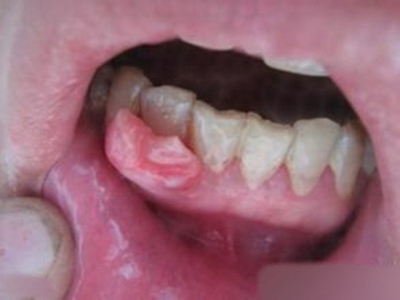

牙龈瘤是指发生在龈乳头部位的炎症反应性瘤样增生物,好发于女性,前磨牙区最为常见。牙龈瘤来源于牙周膜及牙龈的结缔组织,因其无肿瘤的生物学特征和结构,故非真性肿瘤,但切除后易复发,因此切除务必彻底,必要时拔除相关牙齿。

牙龈瘤多发于女性,以青年及中年人为常见,多发生于牙龈乳头部,位于唇、颊侧者较舌、腭侧者多,最常见的部位是前磨牙区。肿块较局限,呈圆形或椭圆形,有时呈分叶状,大小不一,直径由几毫米至数厘米。

肿块有的有蒂,如息肉状;有的无蒂,基底宽广,生长较慢,但在女性妊娠期间可能迅速增大。较大的肿块可以遮盖一部分牙及牙槽突,表面可见牙压痕,易被咬伤而发生溃疡,伴发感染。随着肿块的增长,牙槽骨壁逐渐被破坏,牙可能发生松动、移位。